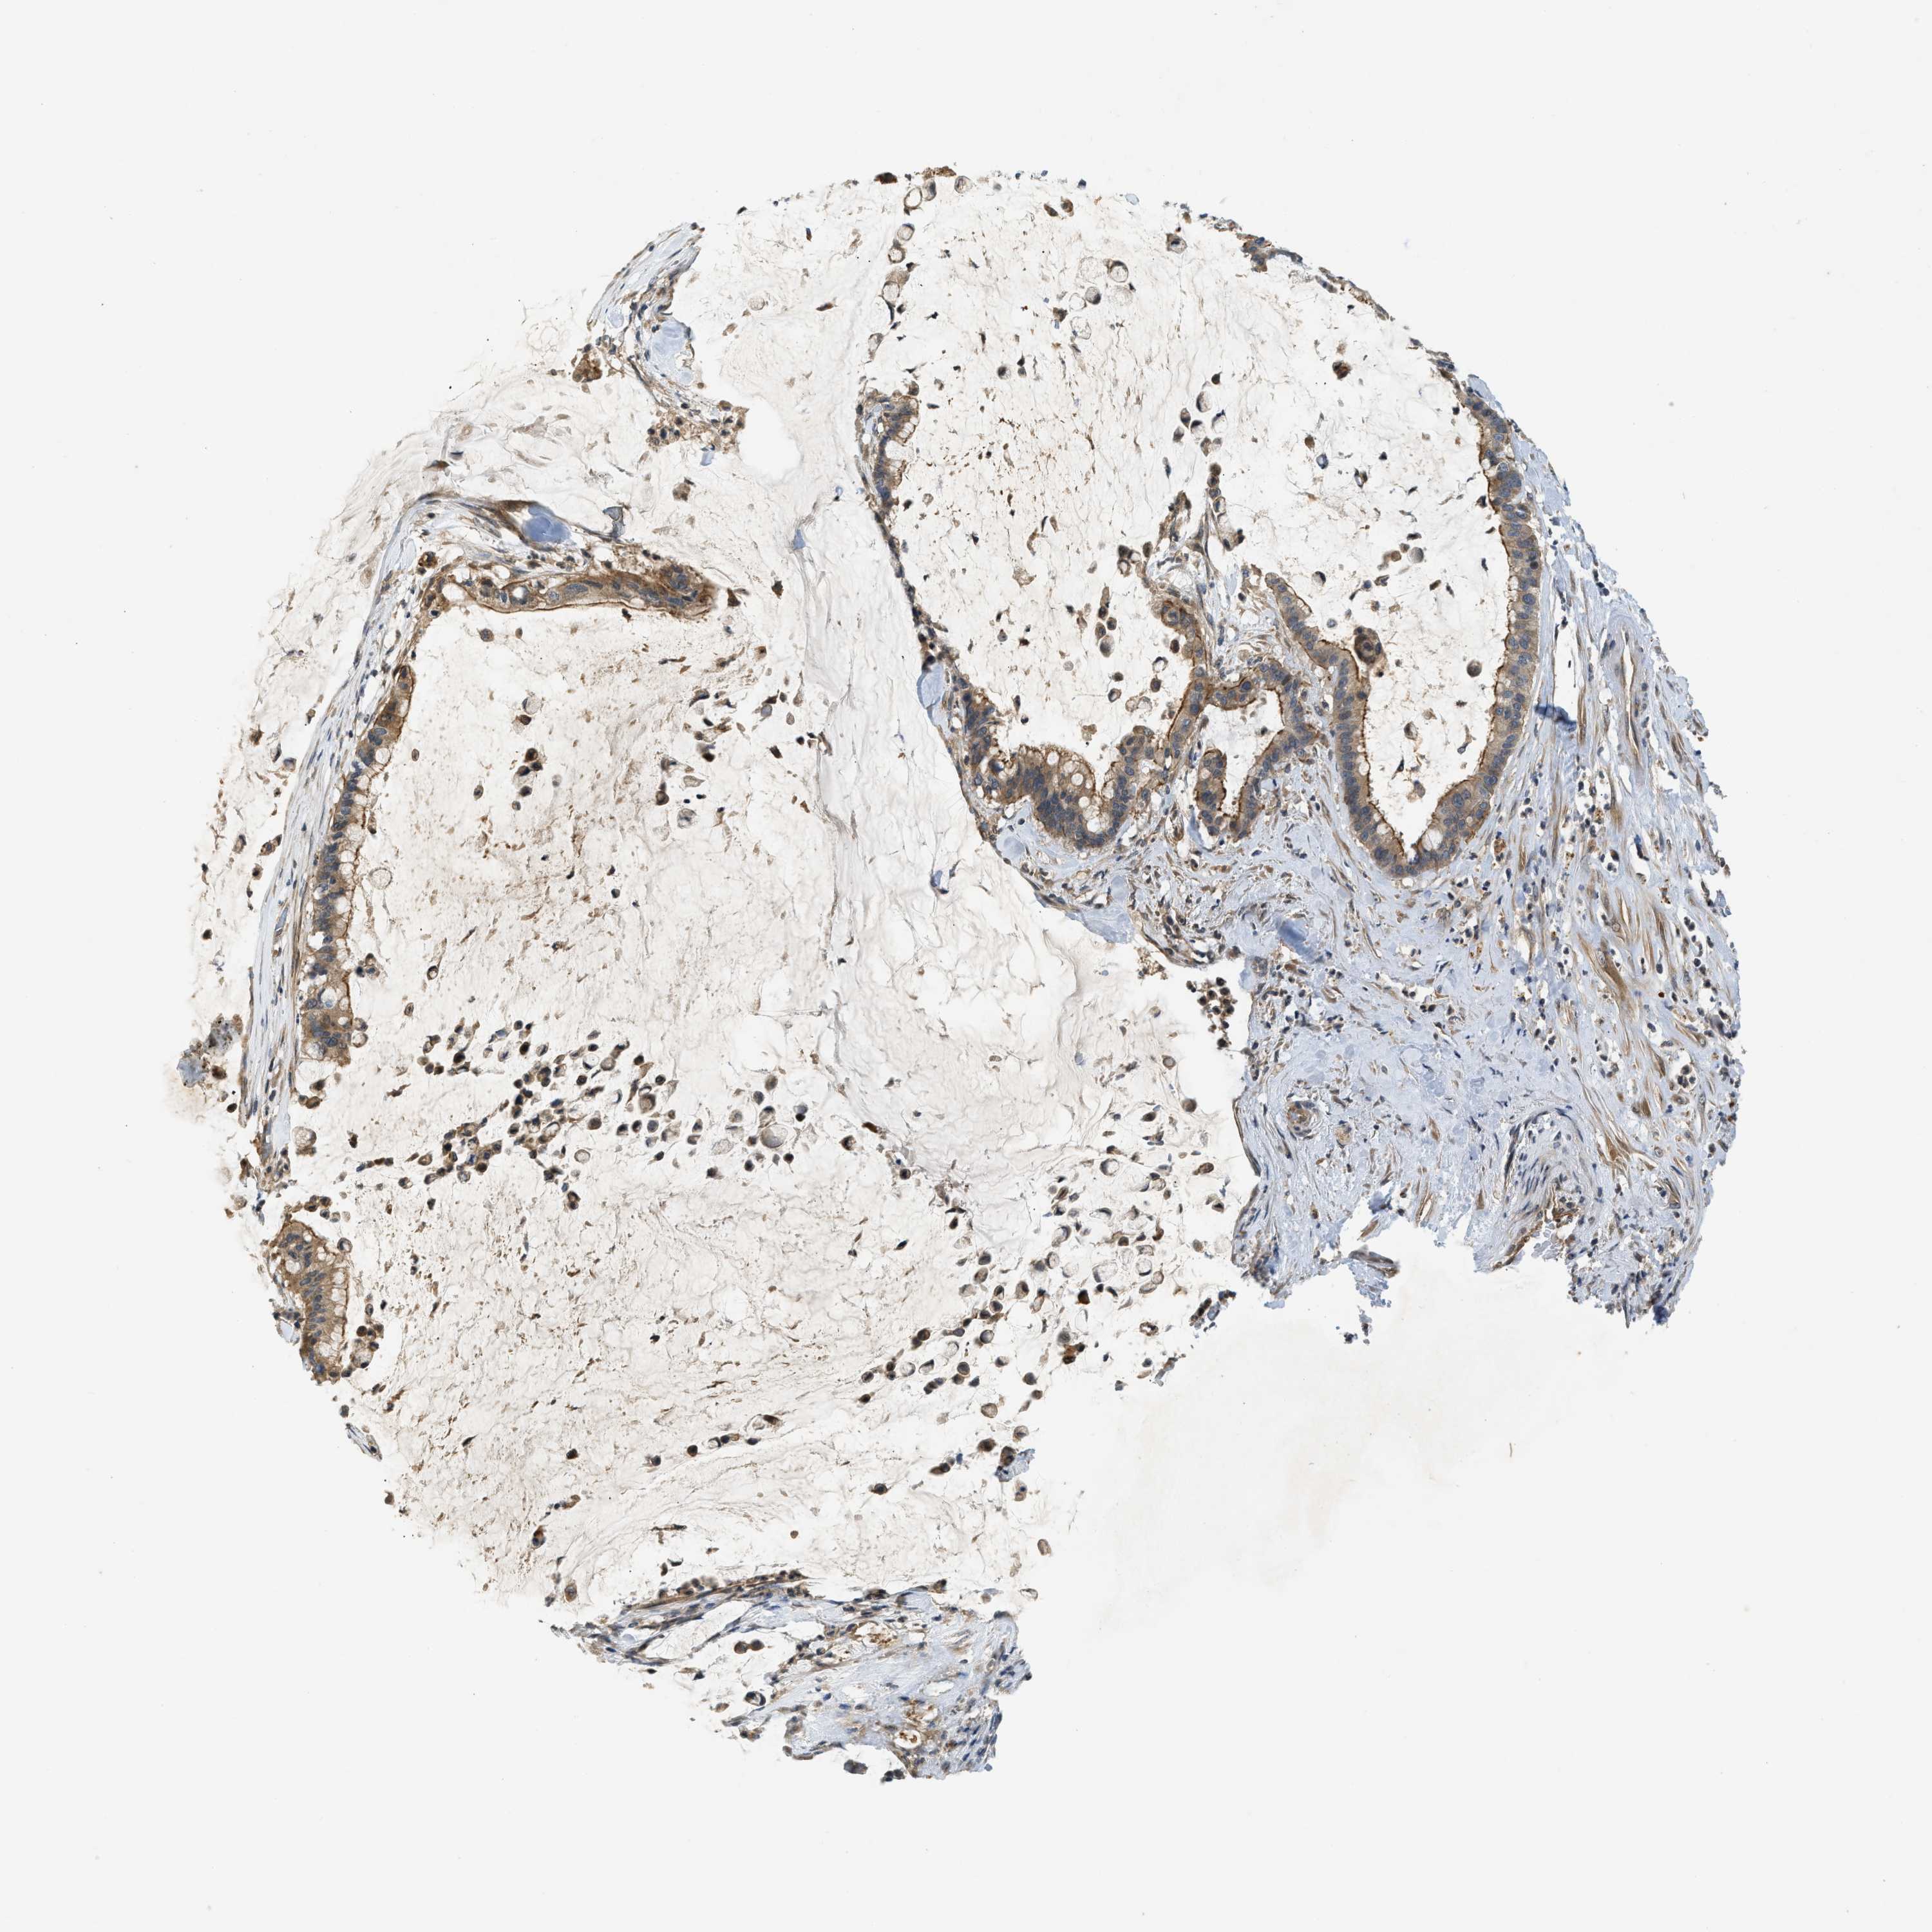

PANCREATIC CANCER - Protein expressioni

A mouse-over function shows sample information and annotation data. Click on an image to view it in a full screen mode. Samples can be filtered based on level of antibody staining by selecting one or several of the following categories: high, medium, low and not detected. The assay and annotation is described here.

Note that samples used for immunohistochemistry by the Human Protein Atlas do not correspond to samples in the TCGA dataset.

Antibody stainingi

Antibody staining in the annotated cell types in the current human tissue is reported as not detected, low, medium, or high, based on conventional immunohistochemistry profiling in selected tissues. This score is based on the combination of the staining intensity and fraction of stained cells.

Each image is clickable and will lead to virtual microscopy that enables deeper exploration of all samples and also displays staining intensity scores, fraction scores and subcellular localization as well as patient and tissue information for each sample.

Antibody HPA024291

Antibody CAB018652

Staining

High

Medium

Low

Not detected

Intensity

Strong

Moderate

Weak

Negative

Quantity

>75%

75%-25%

<25%

None

Location

Nuclear

Cytoplasmic/membranous

Cytoplasmic/membranous,nuclear

Adenocarcinoma, NOS